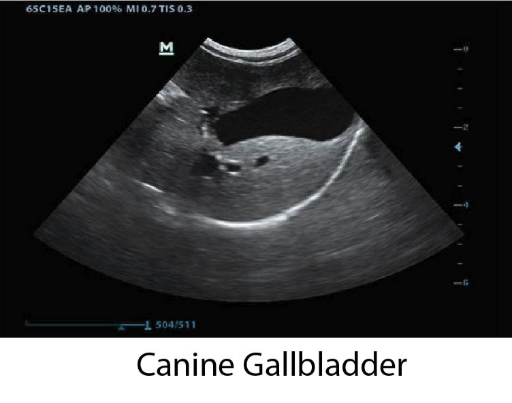

DP-50 Vet е балансирана ултразвукова система, максималното въплъщение на философията на Mindray Animal – качествена диагностика на достъпна цена.

Преносимия ехограф от ново поколение DP-50 Vet е с тънък и ергономичен дизайн, голям FullScreen монитор с качествен “В” и “цветен” образ, както и със стандартно включени множество възможности и софтуери.

Оборудван с PW доплер, Smart 3D и софтуери с автоматични измервания, DP-50 Vet надминава очакванията на всеки потребител. Компакният нов корпус, повишена мобилност и удобство при работа, правят модела подходящ за множество ветеринарни клинични нужди.